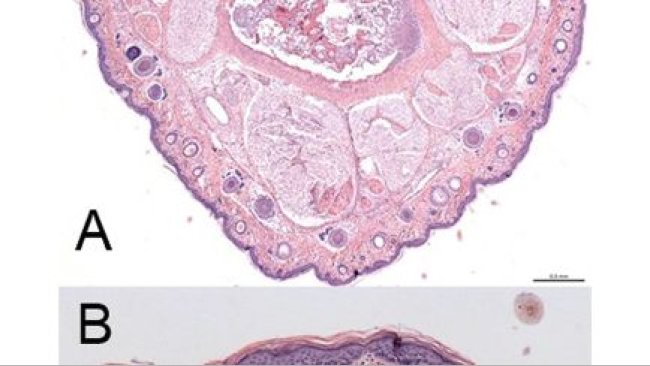

Nei suini, i virus dell'influenza di tipo A ed il Mycoplasma hyopneumoniae (Mhp) sono i principali artefici del complesso respiratorio suino. E' stato dimostrato sperimentalmente in passato che l'infezione in precedenza con Mhp possa esacerbare i segni clinici dell'infezione da H1N1 durante la prima settimana dopo l'inoculazione del virus...Con il fine di comprendere meglio le interazioni tra questi patogeni, questo studio ha avuto come obiettivo valutare le risposte molto precoci (a 5, 24 e 48 h) nei suini dopo l'infezione con H1N1 pre-infettati o meno con Mhp...